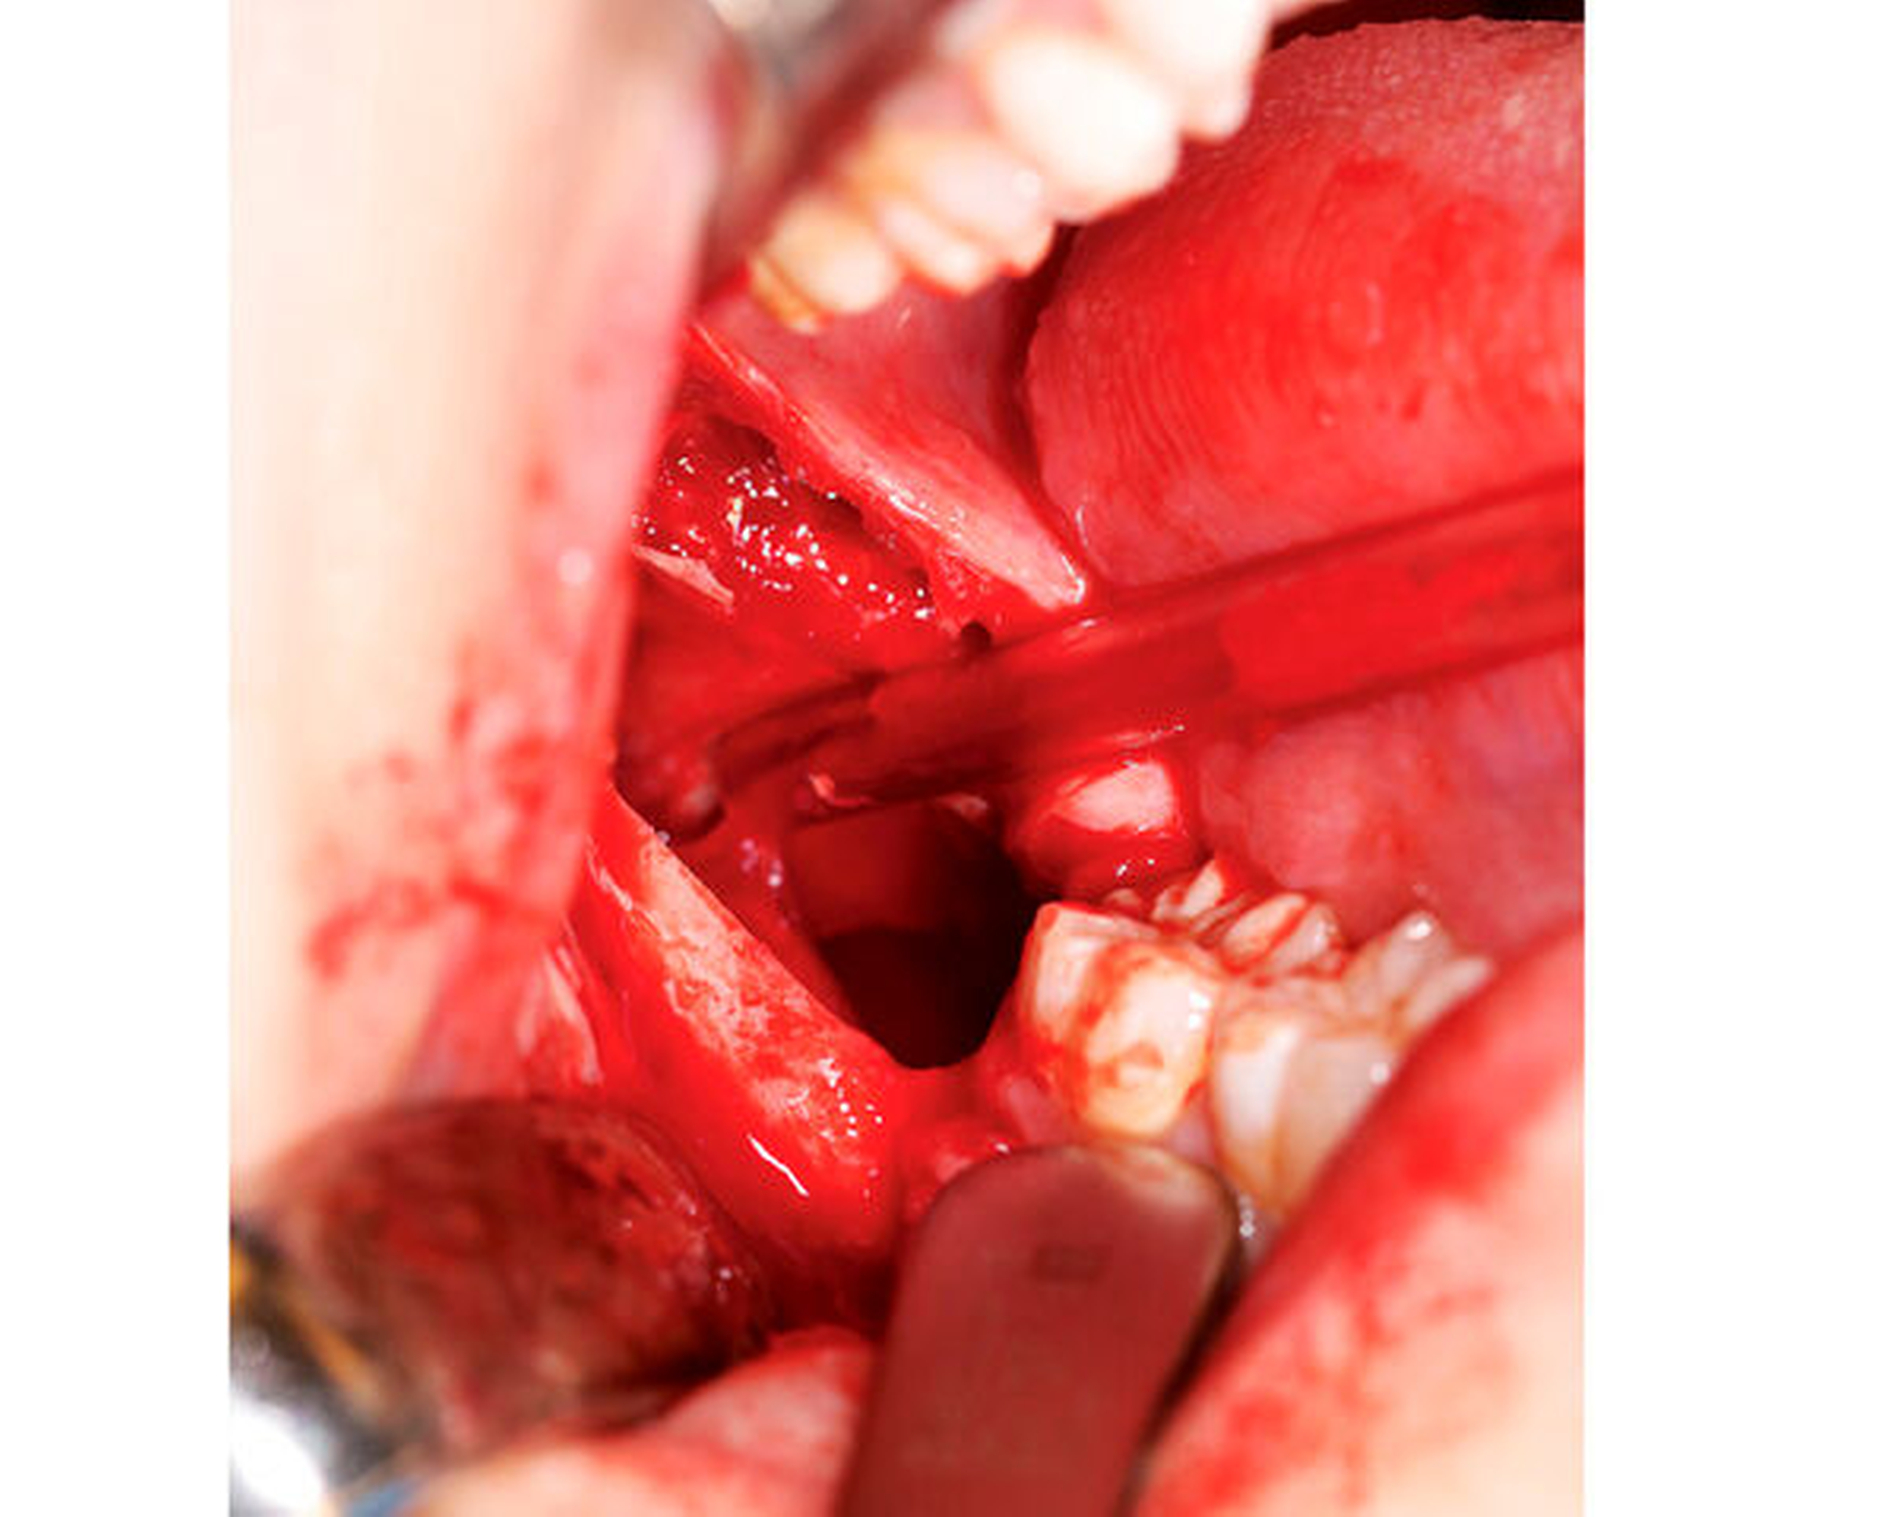

Aufgrund der Gefahr einer Spontanfraktur ebenso wie zur histopathologischen Befundsicherung wird die Indikation zur Zystektomie in Intubationsnarkose gestellt. Diese erfolgt durch Inzision crestal distal des Zahns 47 und im Bereich des aufsteigenden Unterkieferasts mit Bildung eines Mukoperiostlappens. Nach subperiostaler Präparation lässt sich die ausgedehnte Zyste problemlos darstellen (Abbildung 3). Korrespondierend zum vorliegenden radiologischen Befund erreicht die Raumforderung die linguale Knochenkante. Unter Schonung des N. alveolaris inferior werden die Enukleation der Zyste in zwei Teilen und die Entfernung der crestal beteiligten Knochenanteile vorgenommen (Abbildung 4). Nach ausgiebiger Spülung kann der entstandene Defekt nach Einlage von Kollagenschwämmen mittels des vorgelegten Mukoperiostlappens plastisch gedeckt werden.